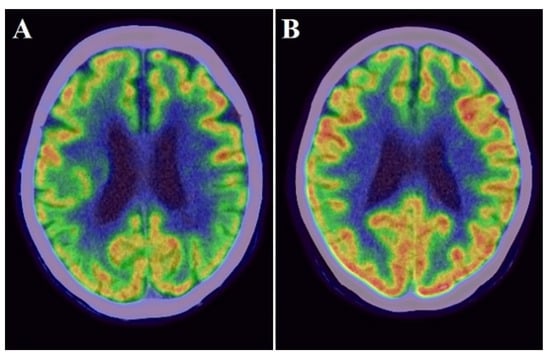

Static PiB-PET and FDG-PET studies were conducted in three-dimensional scanning mode using a Siemens Biograph mCT PET scanner (Siemens) as previously described [,]. The reagents were provided by the PET center of our hospital. Participants received an intravenous bolus injection of PiB [mean ± standard deviation (SD) of radioactivity = 523 ± 47 MBq] and subsequent saline flush in the PiB-PET study. Then, PET images were acquired 50–70 min after the injection. To perform FDG-PET, all participants kept close their eyes and relaxed in a dimly lit room for 10 min before the injection. Then, they received a bolus intravenous injection of 3.0 MBq/kg FDG and subsequent saline flush. PET images were acquired 40–60 min after the injection. The radiation in pre-pose and post-dose samples was measured using a radiation detector for the calculation of injected dose in each participant. All imaging data were reconstructed into a 3.0-mm thick slice, on a 256 × 256 matrix, and at 3.0× magnification with an ordered-subset expectation maximization that includes four iterations and 12 subsets. The reconstructed images had a pixel size of 1.06 mm. The PiB-PET and FDG-PET scans were both spatially normalized to the Montreal Neurological Institute reference space through a customized PET template using Statistical Parametric Mapping version 8 (Wellcome Trust Centre for Neuroimaging, https://www.fil.ion.ucl.ac.uk/spm/) (accessed date 7 October 2021). Regions of interest (ROIs), such as the frontal lobe, temporoparietal lobe, posterior cingulate gyrus, and cerebellum, were determined using the MarsBaR (MRC Cognition and Brain Sciences Unit) ROI toolbox for Statistical Parametric Mapping as described previously []. These ROIs were established as areas with amyloid deposition and decreased cortical glucose metabolism in patients with AD [,]. PiB and FDG uptake was assessed by a standardized uptake value ratio (SUVR). The ROI values were averaged across both hemispheres. The globally standardized uptake value ratio of FDG-PET and PiB-PET was represented as a single mean value for all regions combined (Figure 2 and Figure 3). Higher amyloid uptake was determined using a mean cortical SUVR of 1.4 or higher as the cut off [].

Figure 3.

Examples images of an individual with lower FDG uptake ((A): cortical SUVR value = 0.709) and with higher FDG uptake ((B): cortical SUVR value = 0.874).